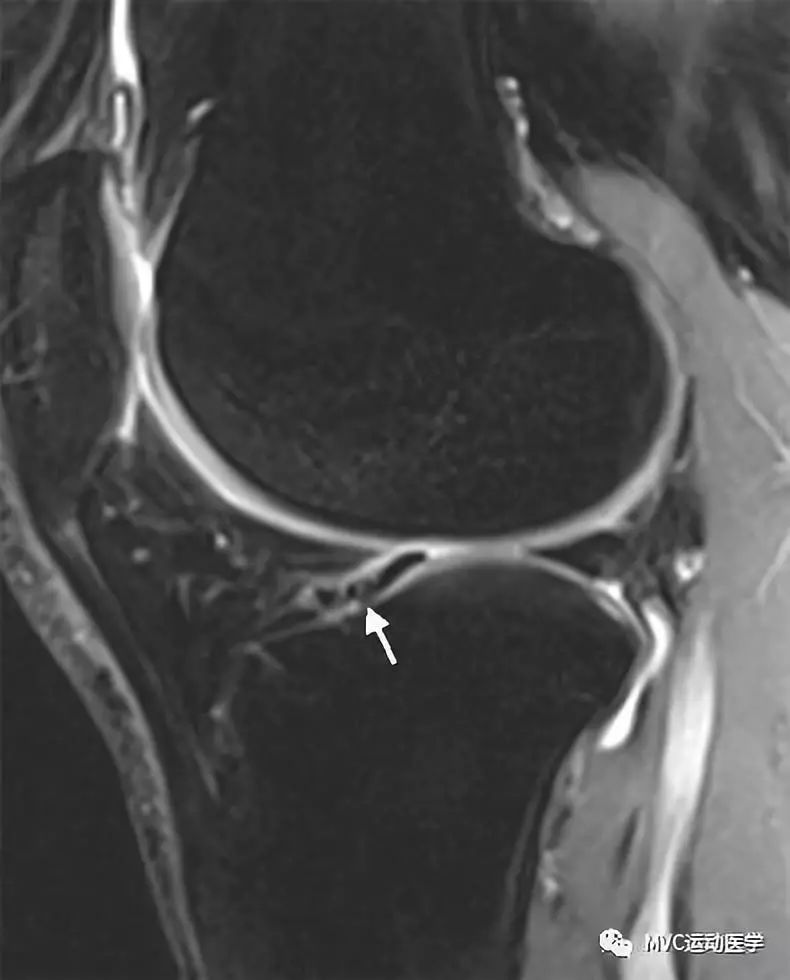

白色箭头所标记为膝横韧带

白色箭头所指为横韧带,黑色箭头所指为内侧半月板前角,位于横韧带正后方

白色箭头所指为横韧带,外侧半月板前角位于横韧带后方

膝横韧带经常容易被误诊为半月板前角撕裂或损伤,我们需要知道有这根韧带,而且要知道它特殊的解剖位置和半月板的形态是否正常,从而与半月板前角鉴别;